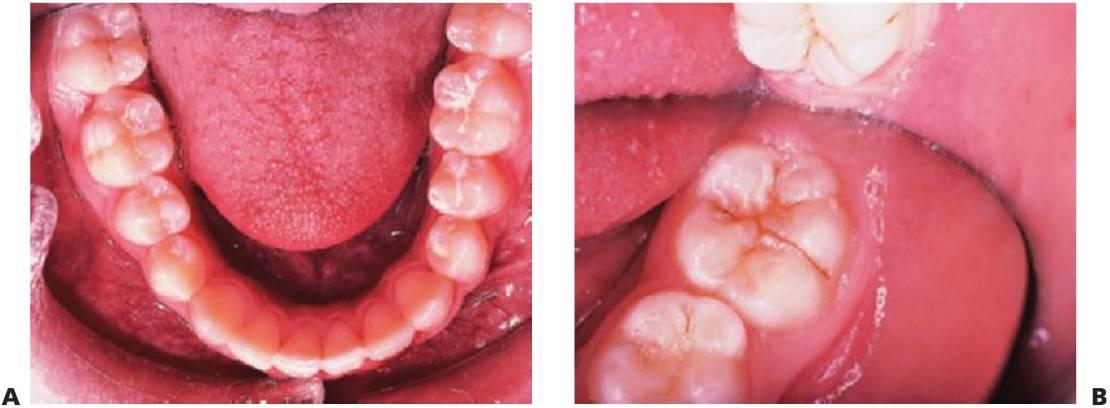

Selladores de fisuras

En las comunidades fluoradas de Australia y Asia, donde el DCAO medio (dientes permanentes cariados, ausentes y obturados) es inferior al 1,0%, la mayoría de las caries se producen en las fosas y fisuras de los primeros molares permanentes. Una forma sencilla y económica de prevenir las caries de fosas y fisuras es mediante el uso de selladores de fisuras. Las indicaciones para un sellador de fisuras son controvertidas. Tomando como base una población, se ha sugerido que sólo se deben colocar selladores de fisuras a los niños que presentan un riesgo moderado de caries. Sin embargo, ya que casi el 90% de la población mayor de 18 años tienen algunas caries (sobre todo en los primeros molares permanentes), se debería valorar la necesidad de colocar selladores de fisuras a lo largo de la erupción de la dentición permanente a todos los niños. La prescripción del tratamiento se debe realizar de acuerdo a las necesidades individuales de cada paciente (fig. 5.9).

Los selladores de fisuras no deben considerarse restauraciones permanentes, por lo que contemplar su uso requiere un diagnóstico exhaustivo y practicar una técnica minuciosa. Se deben examinar todas las radiografías de los dientes antes de la colocación del sella dor de fisuras. Otras acciones para pulir el diagnóstico antes de sellar las fisuras incluyen el uso de fresas miniatura para estudiar las tinciones, la fluorescencia láser, los detectores electrónicos de caries y la microabrasión. Si se observa o se sospecha una caries, es preciso colocar una restauración preventiva de resina.

Indicaciones

- Todos los molares permanentes de niños en riesgo medio o elevado de caries (v. tabla 3.1). Es preciso sellar los premolares de los niños en alto riesgo.

- En niños de bajo riesgo, sólo hay que sellar las fisuras profundas y retentivas.

- Los dientes temporales posteriores de niños en riesgo alto de caries.

La valoración del riesgo debería continuar durante la adolescencia, incluso cuando el riesgo de caries fuera inicialmente bajo, pues el riesgo puede variar y el sellado de las fisuras sigue siendo protector en la edad adulta.